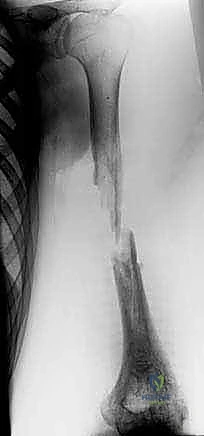

2. الإصابات والحوادث الشديدة (Severe Trauma)

حوادث السير المروعة، السقوط من ارتفاعات شاهقة، أو الإصابات بطلقات نارية غالباً ما تؤدي إلى تهشم العظام وفقدان أجزاء كبيرة منها في مكان الحادث. الترقيع الوعائي يعيد بناء الهيكل العظمي للطرف المصاب بكفاءة.

- بناءً على صور الأشعة السينية التي تؤكد بدء التئام العظم المنقول مع العظم الأصلي، يسمح الأستاذ الدكتور هطيف بالتحميل الجزئي التدريجي باستخدام العكازات.

- العظم المنقول (الشظية) يبدأ في التضخم (Hypertrophy) استجابة للوزن المحمل عليه، ليصبح تدريجياً في سماكة وقوة العظم الأصلي المفقود.